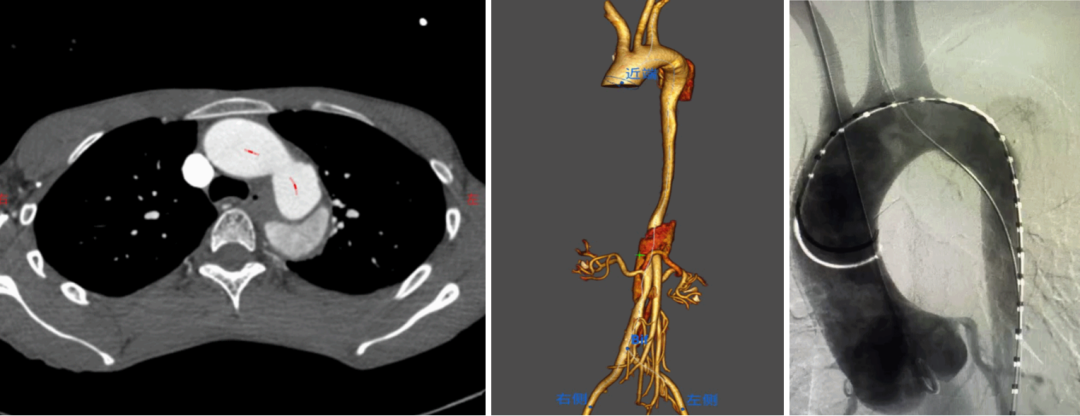

★ Case1:胸主动脉夹层动脉瘤,带分支支架重建LSA+平行支架重建LCCA